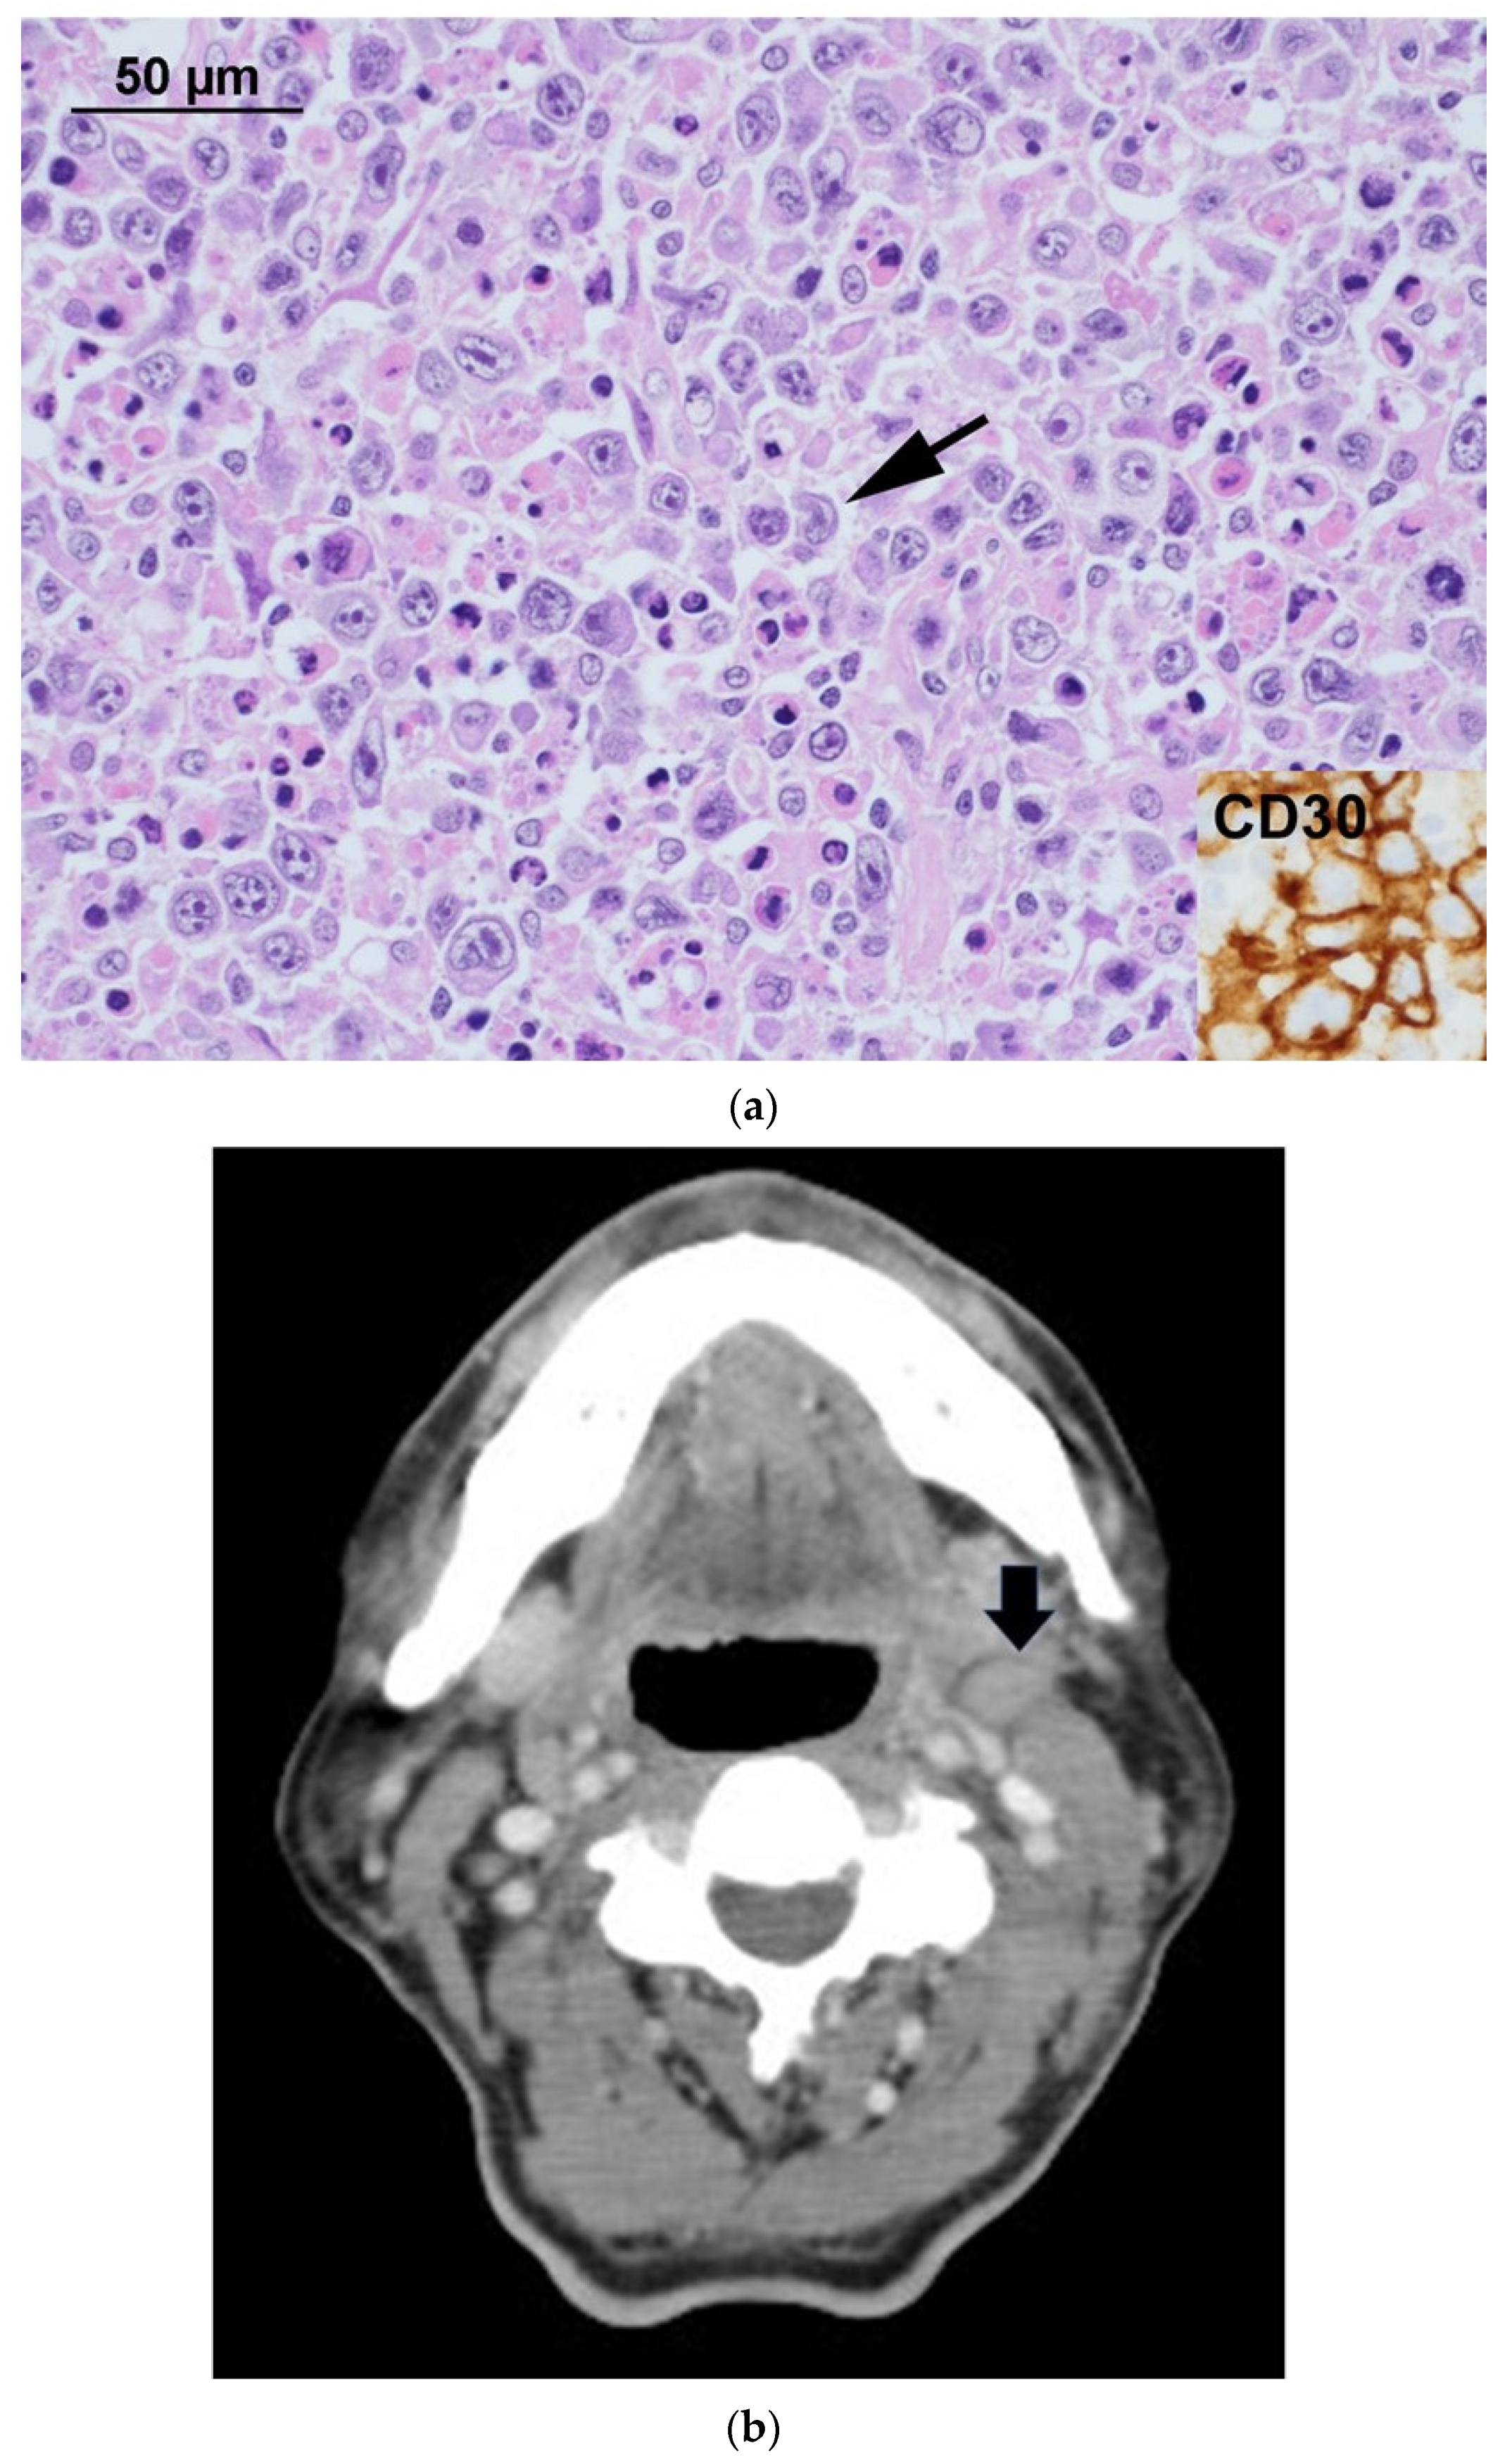

Evolution of 18F-FDG Uptake as a Pitfall of Image Diagnosis for Systemic Anaplastic Large Cell Lymphoma